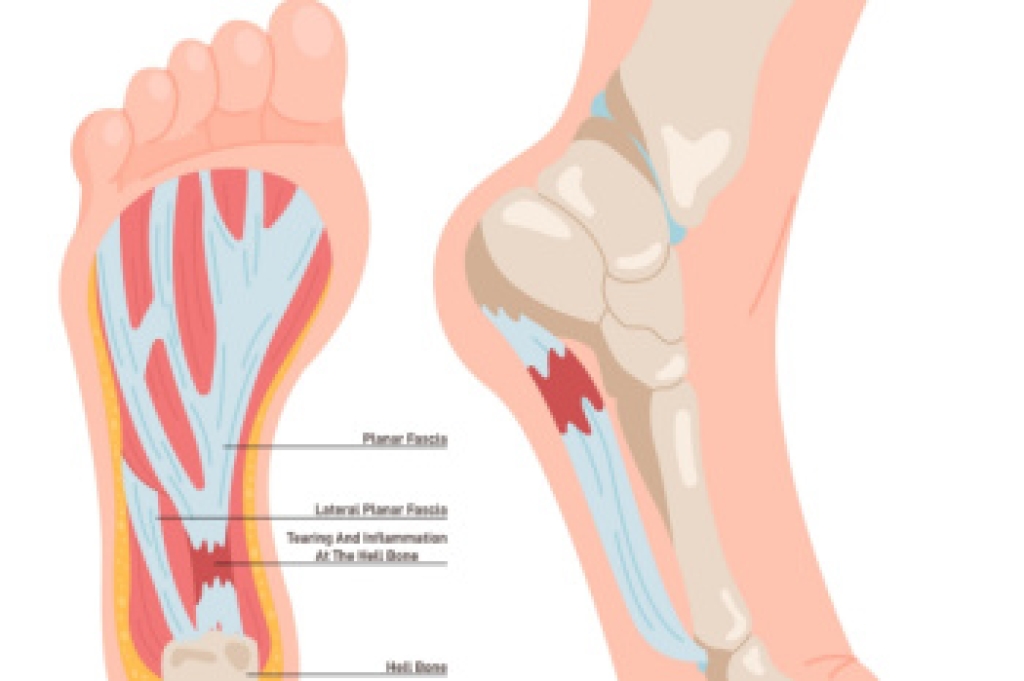

Peripheral neuropathy affects the nerves in the feet, often leading to unusual sensations that can develop gradually. Patients may notice burning, tingling, numbness, or a pins and needles feeling, especially in the toes or soles. The skin may appear normal, but the loss of sensation can make it difficult to detect injuries, increasing the risk of unnoticed wounds. Some individuals also experience sharp or shooting pain, particularly at night. Common causes include diabetes, nerve compression, certain medications, or underlying medical conditions that affect nerve health. A podiatrist can evaluate nerve function through a detailed exam and may recommend additional testing to determine the cause. Treatment focuses on managing symptoms, protecting the feet, and improving nerve health with medication, supportive footwear, and targeted exercises. Early attention is important to prevent complications. If you have symptoms of peripheral neuropathy, it is suggested that you make an appointment with a podiatrist.

Neuropathy is a condition that leads to damage to the nerves in the body. Peripheral neuropathy, or neuropathy that affects your peripheral nervous system, usually occurs in the feet. Neuropathy can be triggered by a number of different causes. Such causes include diabetes, infections, cancers, disorders, and toxic substances.

To treat neuropathy in the foot, podiatrists will first diagnose the cause of the neuropathy. Figuring out the underlying cause of the neuropathy will allow the podiatrist to prescribe the best treatment, whether it be caused by diabetes, toxic substance exposure, infection, etc. If the nerve has not died, then it’s possible that sensation may be able to return to the foot.